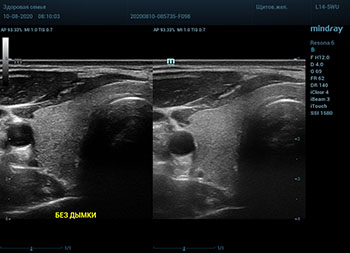

Ультразвуковое оборудование не отстает от современно тренда. В приборах серии Resona, компании Mindray, появилась новая функция постобработки изображения. Имя ей Dehaze. В переводе на наш родной язык – удаление дымки или рассеивание тумана. Инструмент позволяет корректировать интенсивность тумана или дымки. При этом сохраняется общий контраст и детализация картинки. Dehaze также позволяет проявлять детали снимка в гиперэхогенных зонах и снимать артефакты при чрезмерном усилении.

Готовый снимок или видео петля в формате DICOM несет в себе полное нативное изображение. Прибор позволяет, подобно легендарному фотошопу, удалить лишний «туман». Гиперэхогенный диффузный «засвет» изображения, из-за повышенного общего усиления, часто вредит обследованию. Однако без него некоторые вещи не видны. Показать гипоэхогенные участки и скрыть эхогенную дымку и позволяет Dehaze.